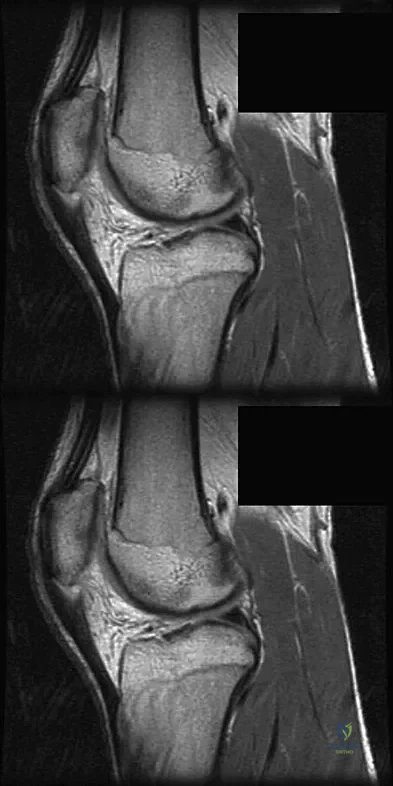

A 36-year-old professional baseball player reports the acute onset of severe right groin pain while attempting to avoid being hit by a baseball while at bat. Examination reveals tenderness, soft-tissue swelling, and ecchymosis in the right groin extending over the medial thigh. MRI scans are shown in Figures 8a and 8b. Management should consist of